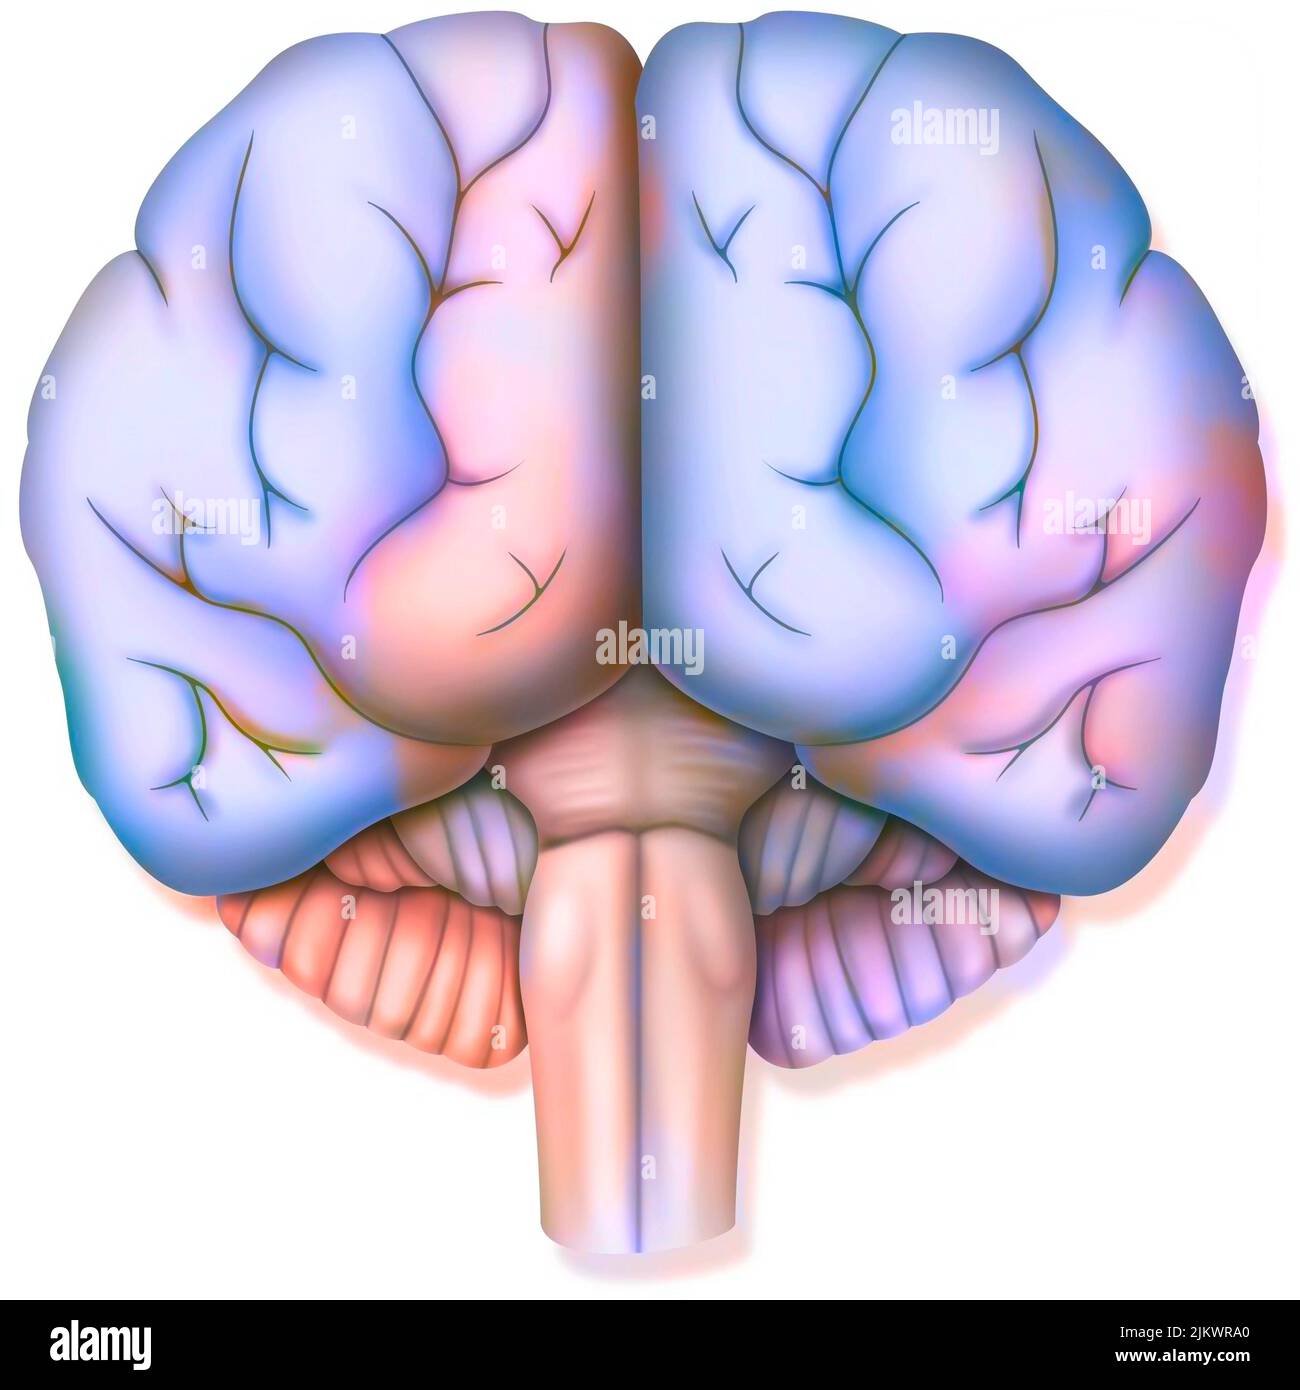

RF2JKWPG7–Troisième étape dans la façon dont le cerveau fonctionne quand vous tombez amoureux: La prise de décision.

RF2JKWPG3–Cerveau dans le chimpanzé avec ses zones (cognitives, auditives, visuelles) et cortex (moteurs, sensoriels).